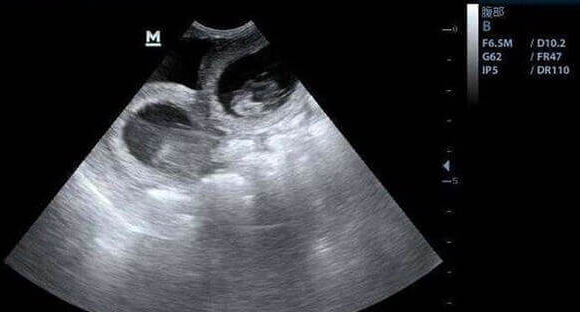

阴道B超通过高频声波穿透盆腔组织,清晰呈现卵巢的立体结构。医生通过测量卵巢体积、计数窦卵泡数量(直径2-9mm的小卵泡),直接评估卵巢储备。例如,育龄期女性单侧卵巢窦卵泡正常范围为5-10个,若双侧总数少于7个,可能提示卵巢功能减退。此外,B超还能监测卵泡生长速度——优质卵泡每日增长约1.5-2mm,若发育迟缓或形态异常,可能预示卵子质量不佳。在促排卵阶段,连续B超监测可精准锁定“扳机时间”(注射破卵针的时机),确保取卵时卵泡处于最佳成熟状态。